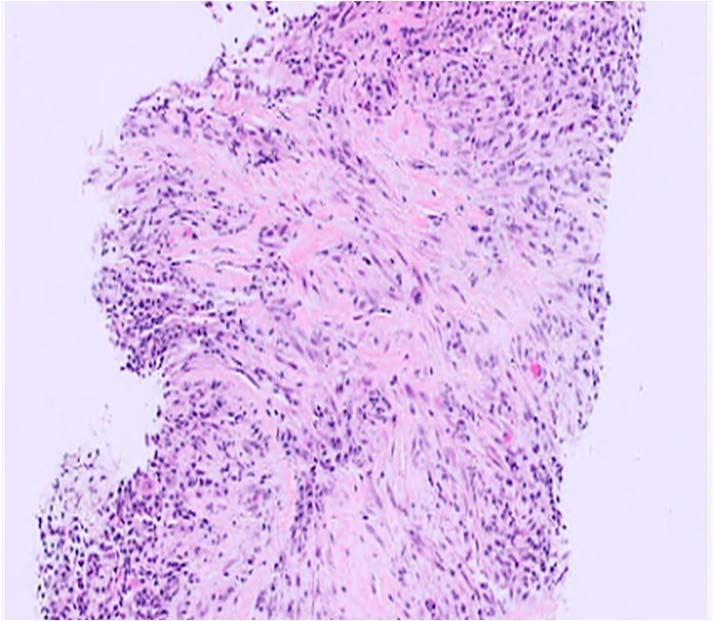

IgG4関連疾患の主な組織病理学的特徴 (文献 1)より)

| 組織学的所見 | 特徴 | 組織学的顕微鏡写真 |

|---|---|---|

| 花むしろ様線維症(Storiform Fibrosis) | リンパ形質細胞性炎症が散在する紡錘体細胞とコラーゲン束の花むしろ様配置。このパターンでは、線維化組織は、側転のスポークに似た、炎症病巣の周囲に放射状に広がる渦巻き状または渦巻き状に配置されます。この独特の線維構造は、この疾患の特徴として広く見なされており、その組織学的認識に大きく貢献しています。 (HE染色、×100) | ![]() |